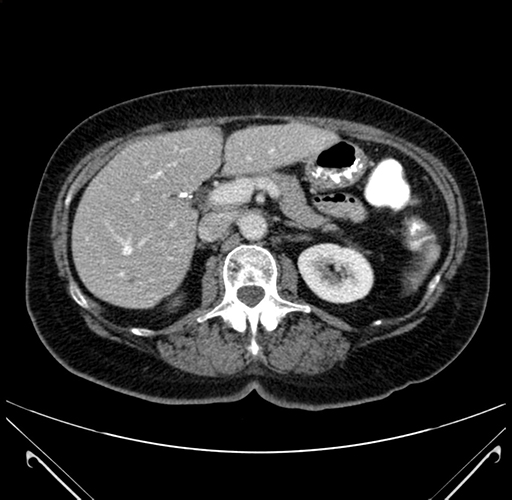

Pre-Chemo: Axial Venous

Axial Venous